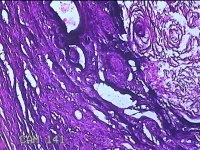

下颌部包块

性别

男

年龄

47岁

临床诊断

皮脂腺囊肿

一般病史

发现下颌部包块3年余,无疼痛及不适。

标本名称

大体所见

灰白暗红色带皮肤结节1.5x1.3x0.8cm一个,表面糜烂,切开结节呈实性,切面灰白粉红色,质软。

图1